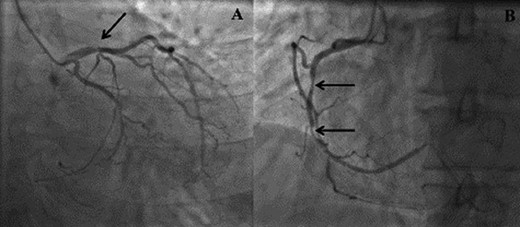

We report on a 57-year-old gentleman who initially presented with a 6-month history of heavy central chest pain, back and shoulder pain and shortness of breath on exertion (New York Heart Association Classification (NYHA) III, Canadian Cardiovascular Society Angina Classification (CCS) II). He suffered an inferior myocardial infarction in 2007 and has a known bicuspid aortic valve under follow-up. Risk factors for ischaemic heart disease include current smoking and a positive family history of heart disease on his maternal side. On admission, a transoesophageal ECHO (TOE) (Fig. 1) and cardiac magnetic resonance imaging (MRI) (Fig. 2) were carried out and demonstrated the bicuspid aortic valve with a mixed stenosis/regurgitation pattern (moderate–severe) (Fig. 1A). In addition, marked left ventricular dilatation and an inferior LVA extending from the base to the mid-cavity of the left ventricle measuring 4.5 cm across the orifice (Fig. 1B) were seen. The aneurysm was thin walled, with dyskinetic motion with evidence of a dense thrombus adherent to the wall. The inferior wall was noted to be akinetic and non-viable. Preoperative LVEF was 60%. The angiogram showed stenosis of the right coronary artery (Fig. 3B) in the mid-segment together with distal left anterior descending disease (Fig. 3A).

(A) Right anterior oblique (RAO) view demonstrating distal left anterior descending disease. (B) Left anterior oblique (LAO) view demonstrating mid right coronary artery disease.